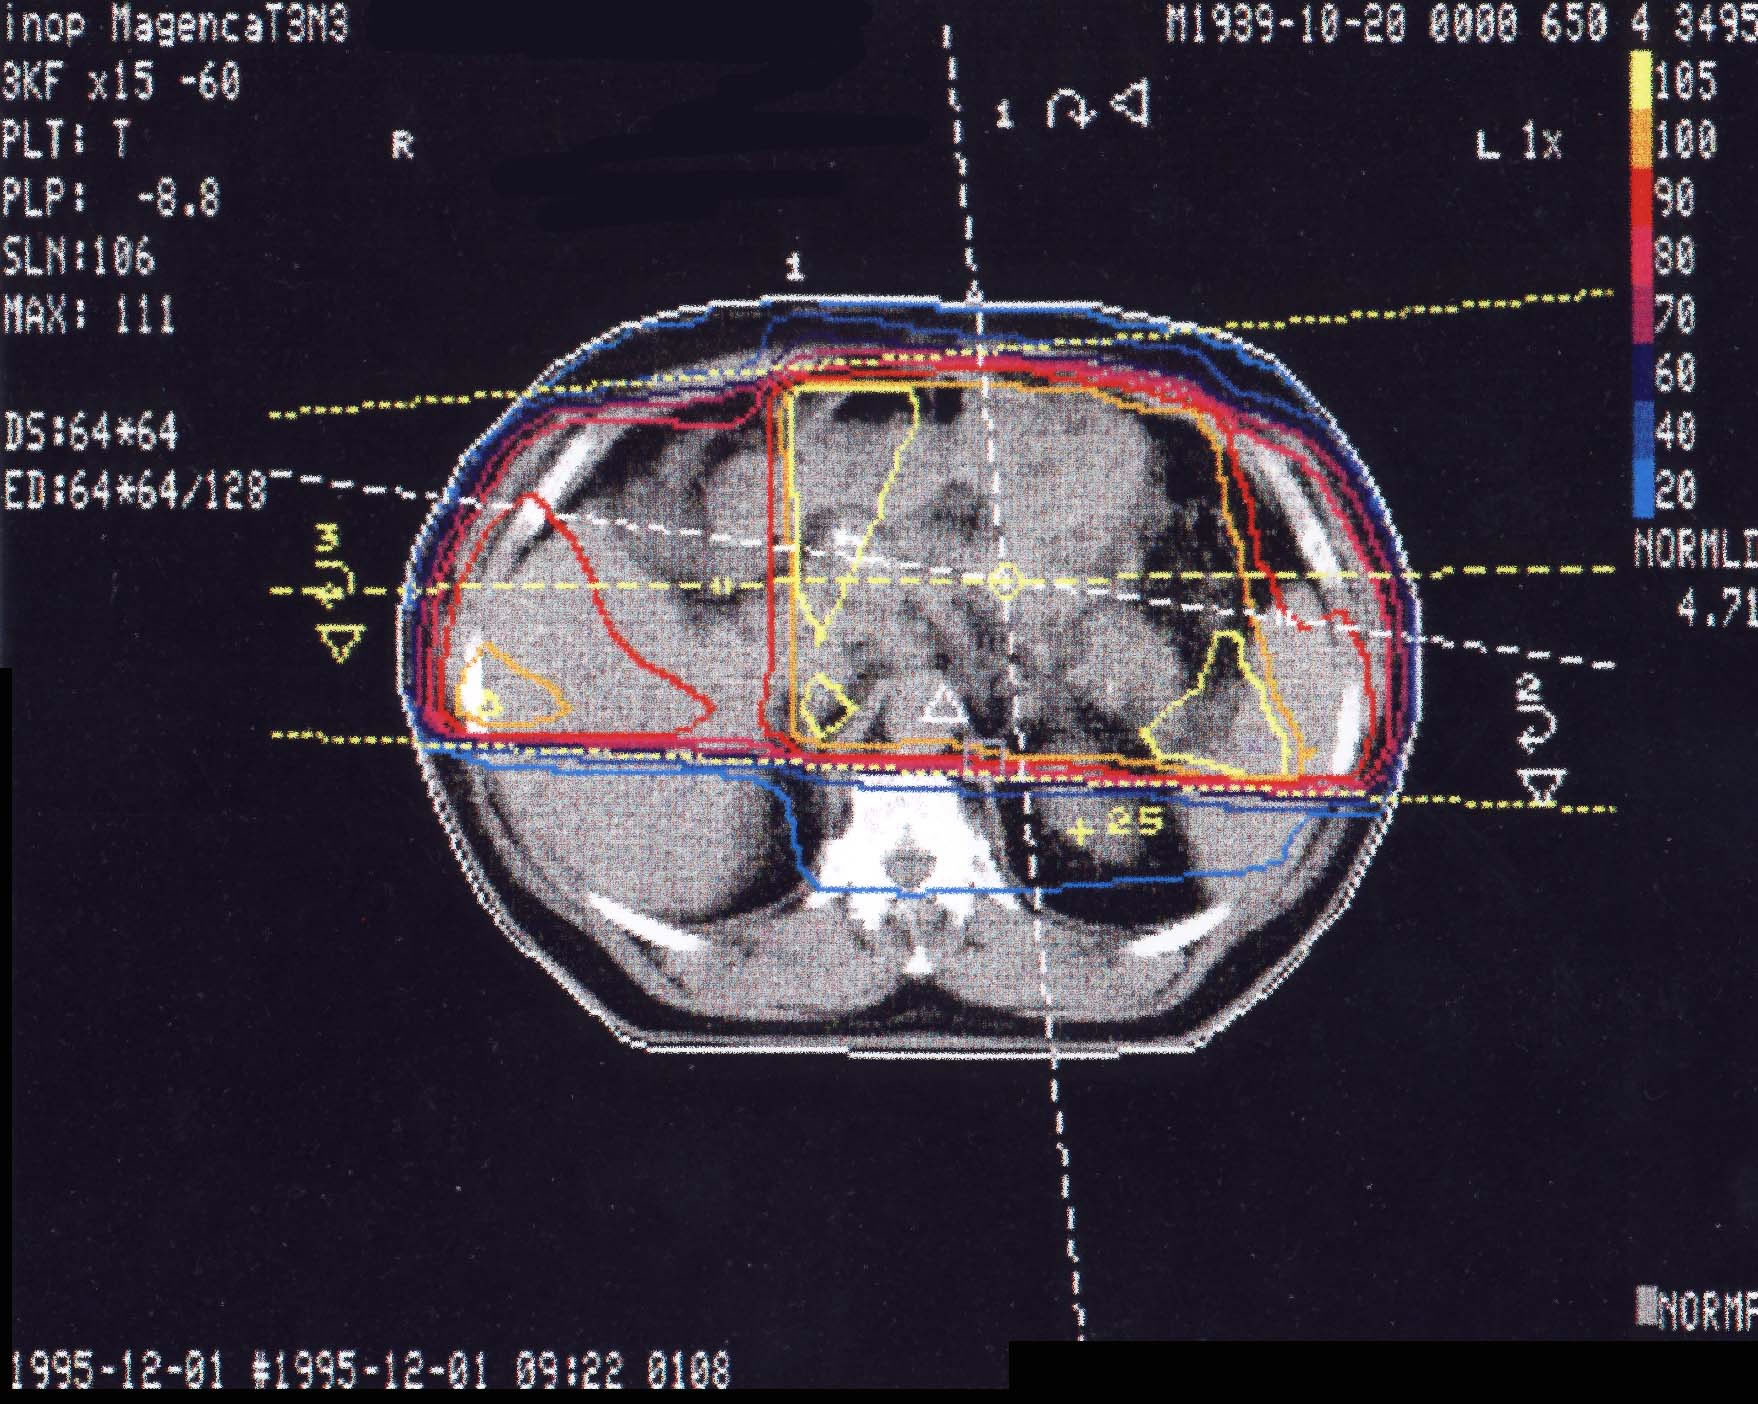

Tumore des Magens: Bestrahlungsplan

Bestrahlungspläne